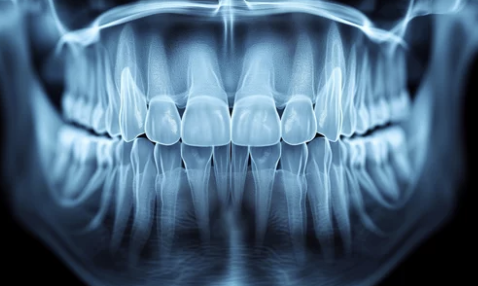

치과에서 신경치료를 받은 후 잇몸이 붓거나 통증이 지속되는 경우가 있습니다.

신경치료는 충치가 심하게 진행된 경우 시행하는 치료로,

치아 내부의 염증을 제거하고 신경을 치료하는 과정입니다.